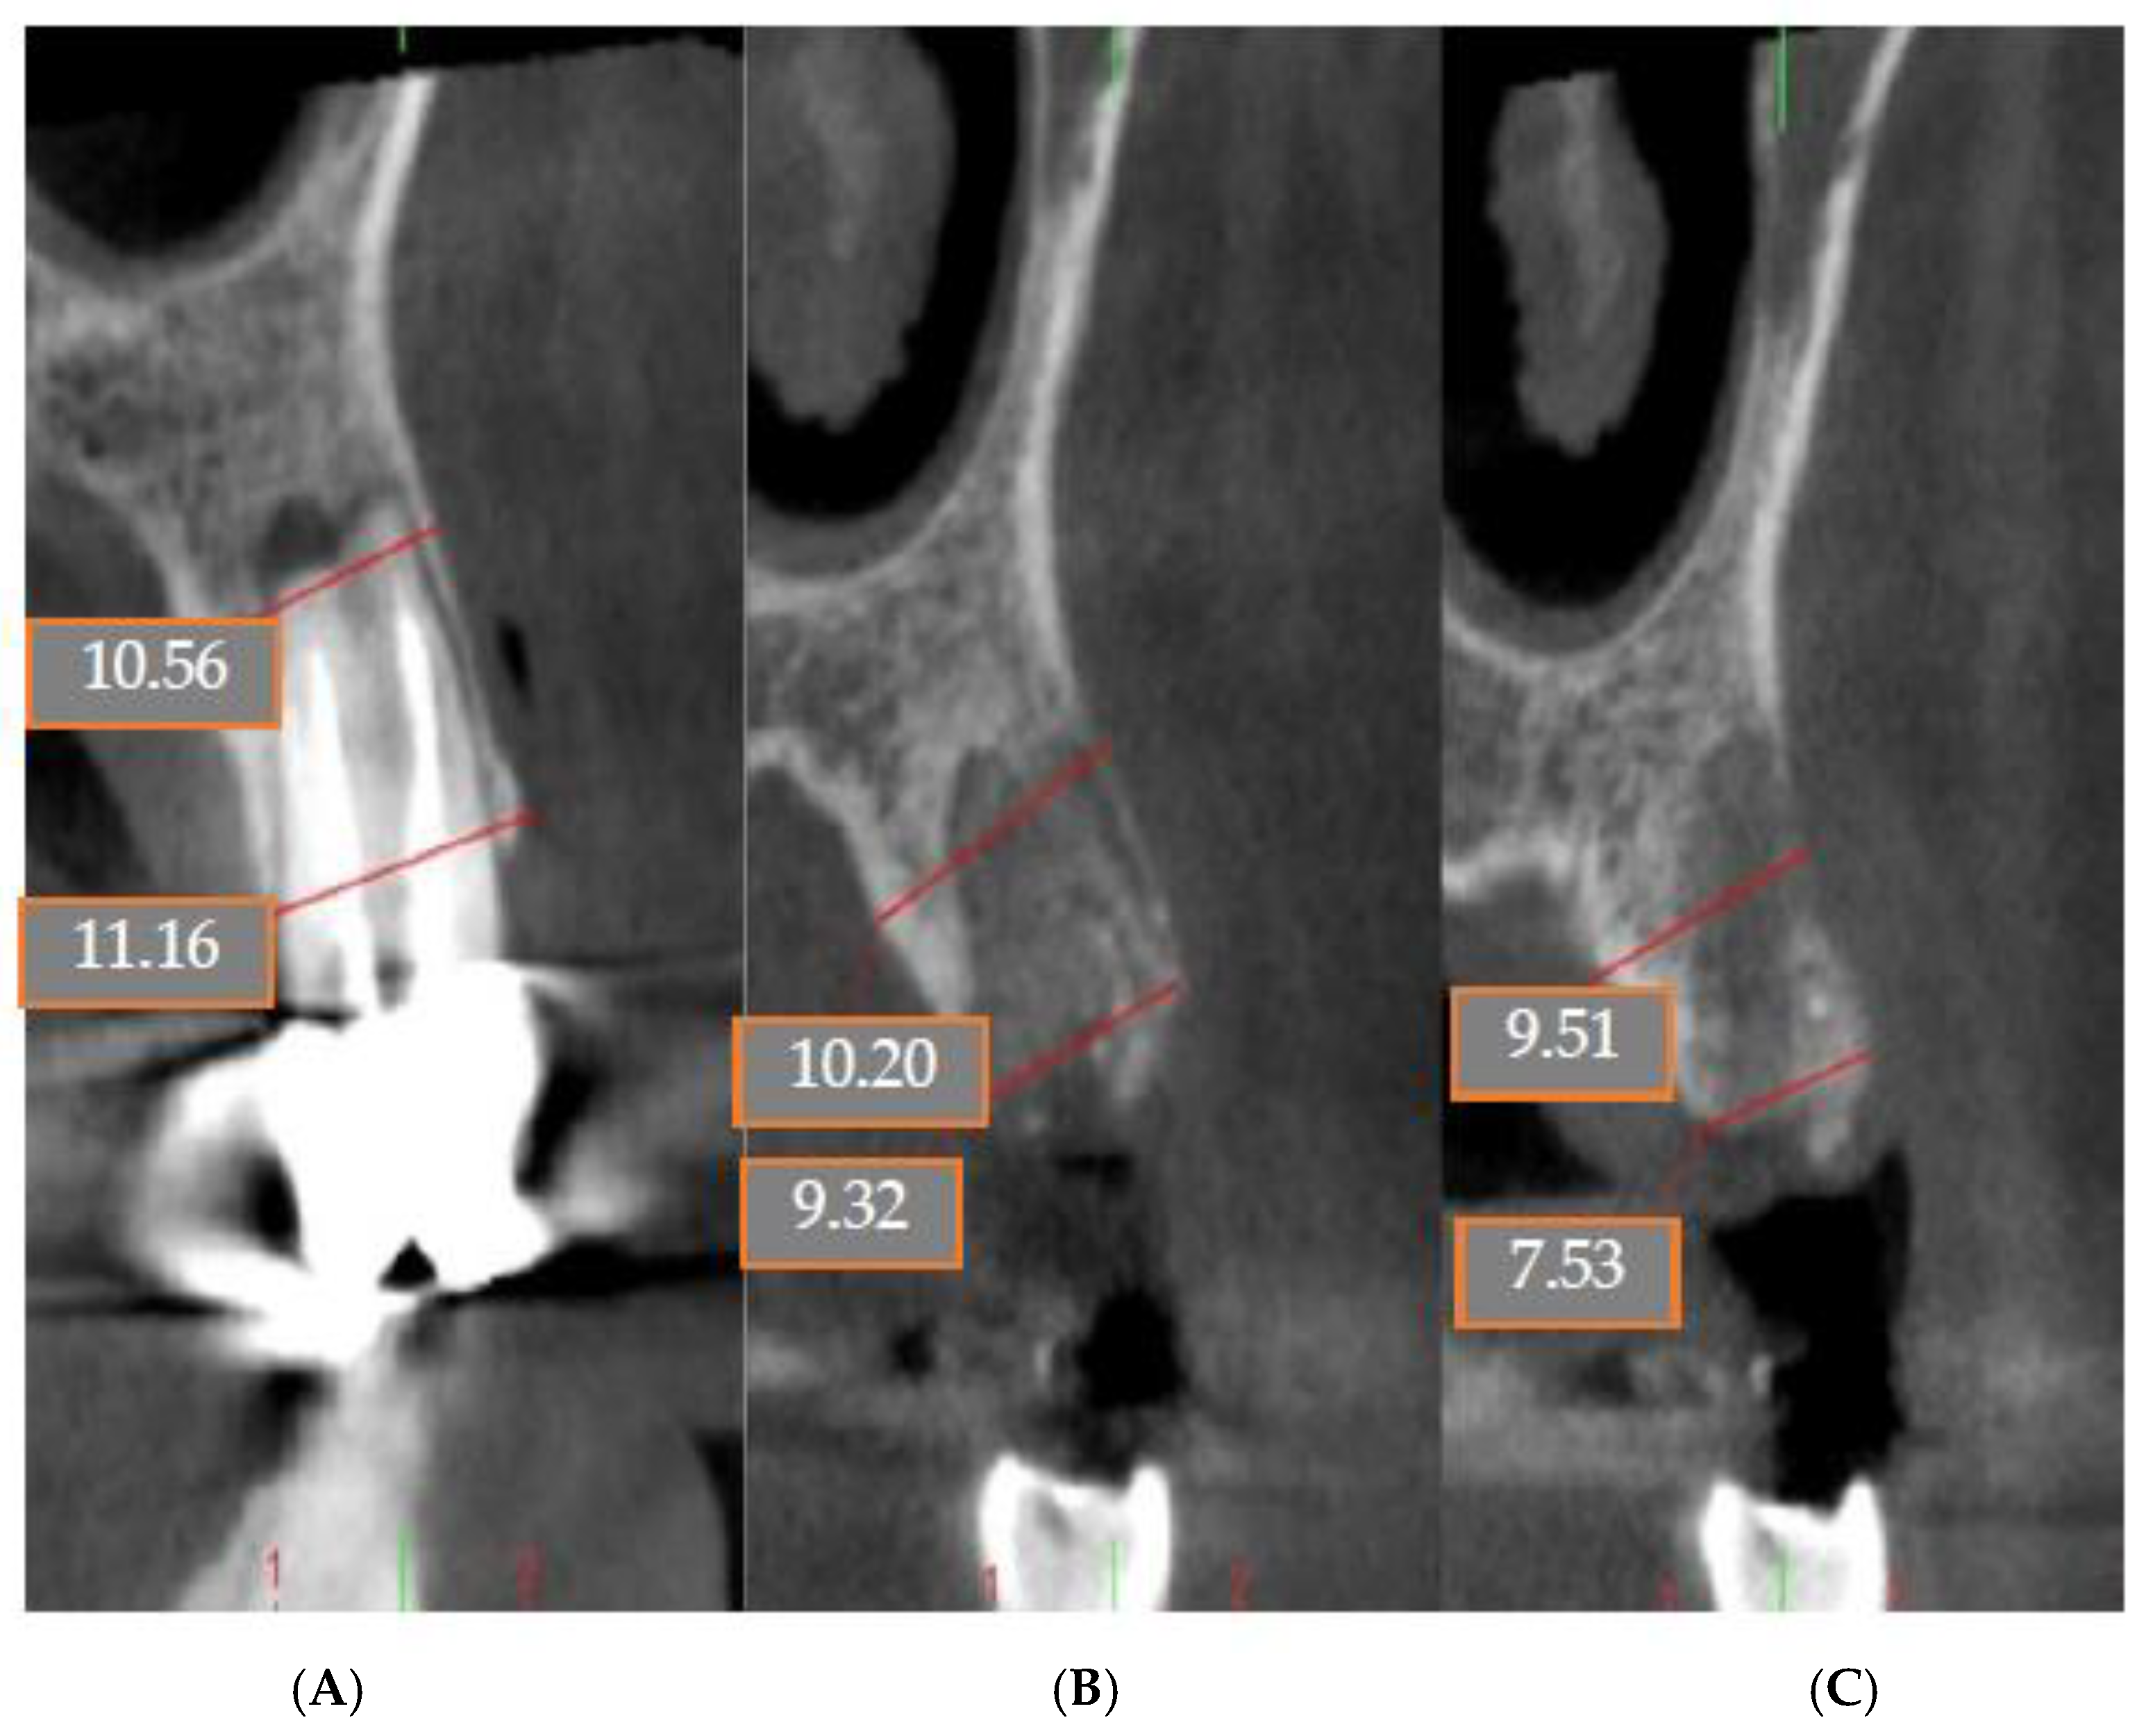

4.1. Patient No. 1

4.2. Patient No. 2

4.3. Patient No. 3

4.4. Patient No.4

4.5. Patient No.5

4.6. Patient No.6